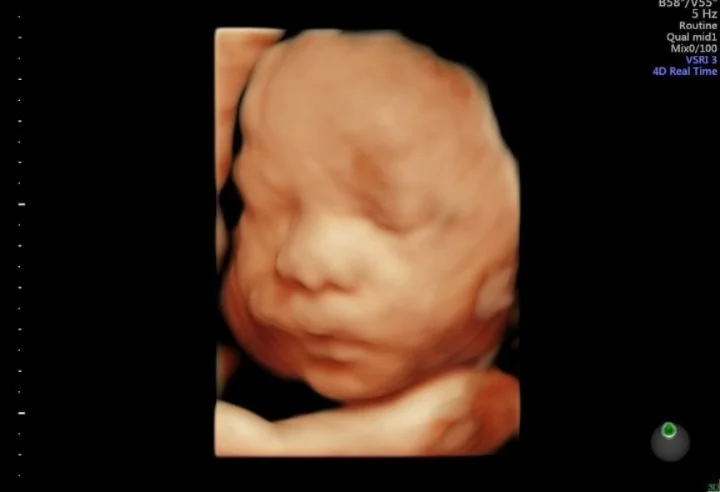

Our state of the art technology allows us to see your baby in a whole different way! With HD Live imaging, we can watch your baby wiggle, smile and yawn all in real time!